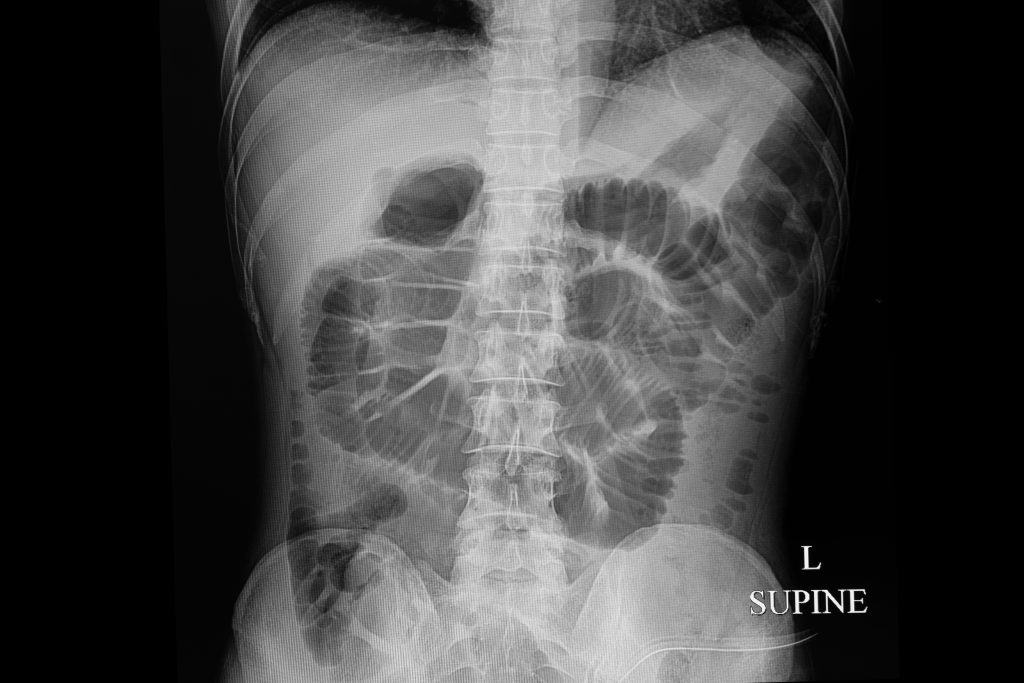

Do ove pojave u probavnom sustavu dolazi jer nema normalnog protoka hrane i crijeva ne vrše svoju funkciju izbacivanja otpadaka iz ljudskog tijela, što zapravo predstavlja oblik paralize crijeva. Može se dijeliti s obzirom na mjesto nastanka na pojavu visokog ileusa koji se nalazi u tankim crijevima, te na pojavu niskog ileusa kod debelog crijeva.

Kada stolica izostane par dana simptomi koji se popratno javljaju su bolovi u trbuhu koji su prisutni i na najmanji dodir trbuha, te nadutost trbuha. Moguće su mučnine i osjećaj gađenja na hranu, te kod nekih i osjećaj povraćanja i samo povraćanje žućkasto zelenog sadržaja. Jako kruljenje je prisutno, te pri tome uz izostanak stolice izostaju i plinovi iz crijeva.